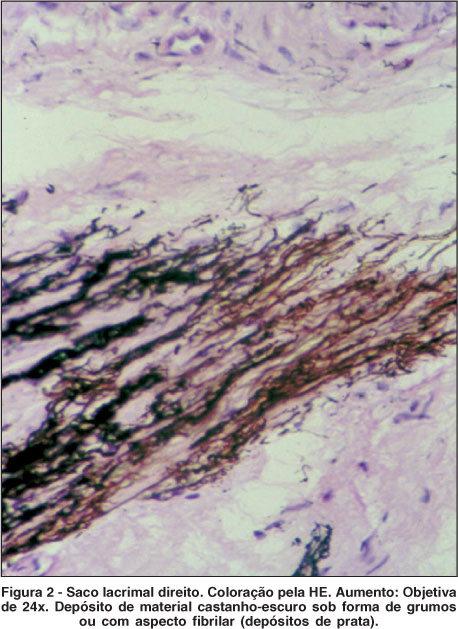

Durante a DCR do OD, observou-se um saco lacrimal de coloração negra (Figura 1). E realizou-se a biópsia do saco lacrimal (Figura 2).

A comprovação da argirose foi feita pela biópsia realizada na conjuntiva bulbar inferior de AO, nos sacos lacrimais de AO e canalículo lacrimal superior do OE. Todos mostraram aspecto histológico semelhante com impregnação sob forma de grumos ou aspecto fibrilar por material de coloração castanho-escura, relatado em estudos sobre o saco lacrimal. Os dois estudos afirmam que o depósito ocorre principalmente no tecido fibroelástico(3,8).